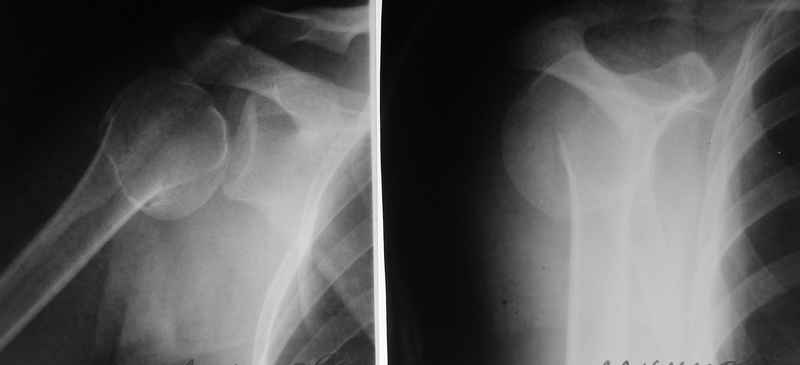

По Neer операцию рекомендовали только тогда, когда угол между диафизом и головкой составляет около 45 градусов, и переломы с меньшим углом смещения считали благоприятным для функционального результата.

Хотя "варусная импакция" в проксимальном отделе плеча срастается хорошо консервативными мерами, но в результате при восстановлении такие больные теряют часть отведения, и тем более у больной варус осложнен еще сгибанием.

Закрытые репозиции без фиксации из-за вторичного смещения неэффективны, поэтому рекомендуется репозиция с фиксацией. Методик много, кто чем владеет и отдает предпочтение закрытые-открытые, перкутанные, с блокирующими пластинами, гвоздь, множественными спицами или методом спиц по Лазареву, и осторожно с манипуляциями из=за возможности повреждения аксиллярного нерва - частый вид осложнении.

Неправильно выбранная тактика по фиксации или технические ошибки во время операции могут привести к серьезным осложнениям. Здесь привожу

пример из нашей практики, вроде обычный перелом шейки, фиксированный популярным методом "Сиэтла" - множественными спицами 2.8 мм с резьбой на конце.

При первичном осмотре в поликлинике через 3 недели обнаружили миграцию двух спиц, срочно госпитализированному на второй день перед операцией на всякий случай сделали снимок, одна спица находилась под ключицей в шейном отделе (на снимке).